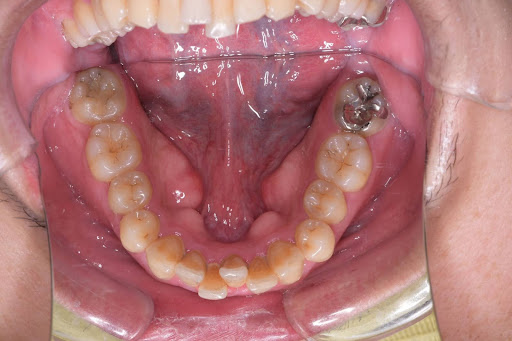

こちらはインビザラインフルプランの術前の写真です。

これがその術後の症例写真です。

フルプランのためかなり全体的に綺麗になりました。